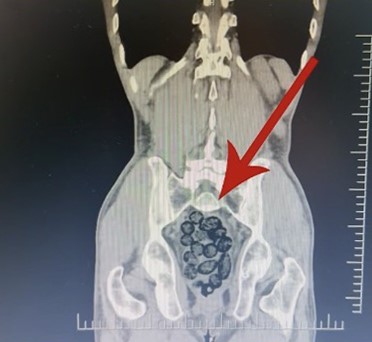

Batman’da durdurulan otobüsteki yabancı şahsın midesinden 64 parça uyuşturucu maddesi metamfetamin çıktı.

Durumundan şüphelenilen yabancı uyruklu bir yolcu üzerinde arama yapıldı. Yapılan incelemeler sonucunda yabancı uyruklu şahsın midesinde 64 Parça halinde toplam 472 gram uyuşturucu maddesi metamfetamin olduğu belirlendi.

Gözaltına alınan şahsın midesindeki uyuşturucu madde çıkartıldı. Emniyetteki işlemlerinin ardından adliye sevk edilen şahıs, çıkarıldığı mahkemece tutuklanarak cezaevine gönderildi.